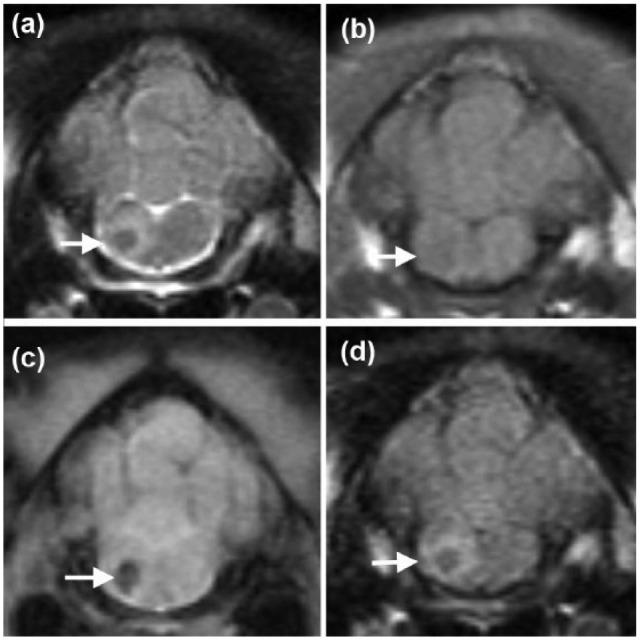

A 6-month-old female domestic shorthair cat was presented with acute onset non-ambulatory right hemiparesis and horizontal nystagmus following an injection attempt in the neck, during which the cat did not cooperate. Magnetic resonance imaging (MRI) revealed a well-defined intra-axial lesion on the right side of the myelencephalon. The lesion was T2-weighted hypointense and T1-weighted hypointense to isointense to grey matter, non-contrast enhancing, with perilesional oedema and signal void on T2*-weighted images. A linear hyperintense lesion in the muscles of the right dorsolateral aspect of the neck on short tau inversion recovery images was also observed. These MRI findings were consistent with iatrogenic brainstem haemorrhage and a muscle needle tract. The cat made a good recovery with just mild residual neurological deficits 6 weeks after the injury.

一只6个月大的雌性家养短毛猫,在颈部注射时未配合,之后出现急性发作的右半身轻瘫且不能行走以及水平性眼球震颤。磁共振成像(MRI)显示延髓右侧有一个边界清晰的轴内病变。该病变在T2加权像上呈低信号,在T1加权像上相对于灰质呈低信号至等信号,无强化,在T2*加权像上有病灶周围水肿和信号缺失。在短tau反转恢复序列图像上,还观察到颈部右背外侧肌肉有一条线性高信号病变。这些MRI表现符合医源性脑干出血和肌肉针道。该猫在受伤6周后恢复良好,仅遗留轻度神经功能缺损。